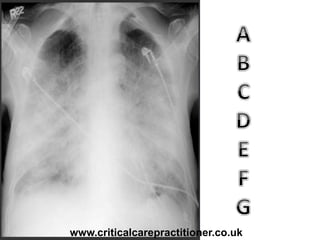

TECHNICALS

Rotation?

Penetration?